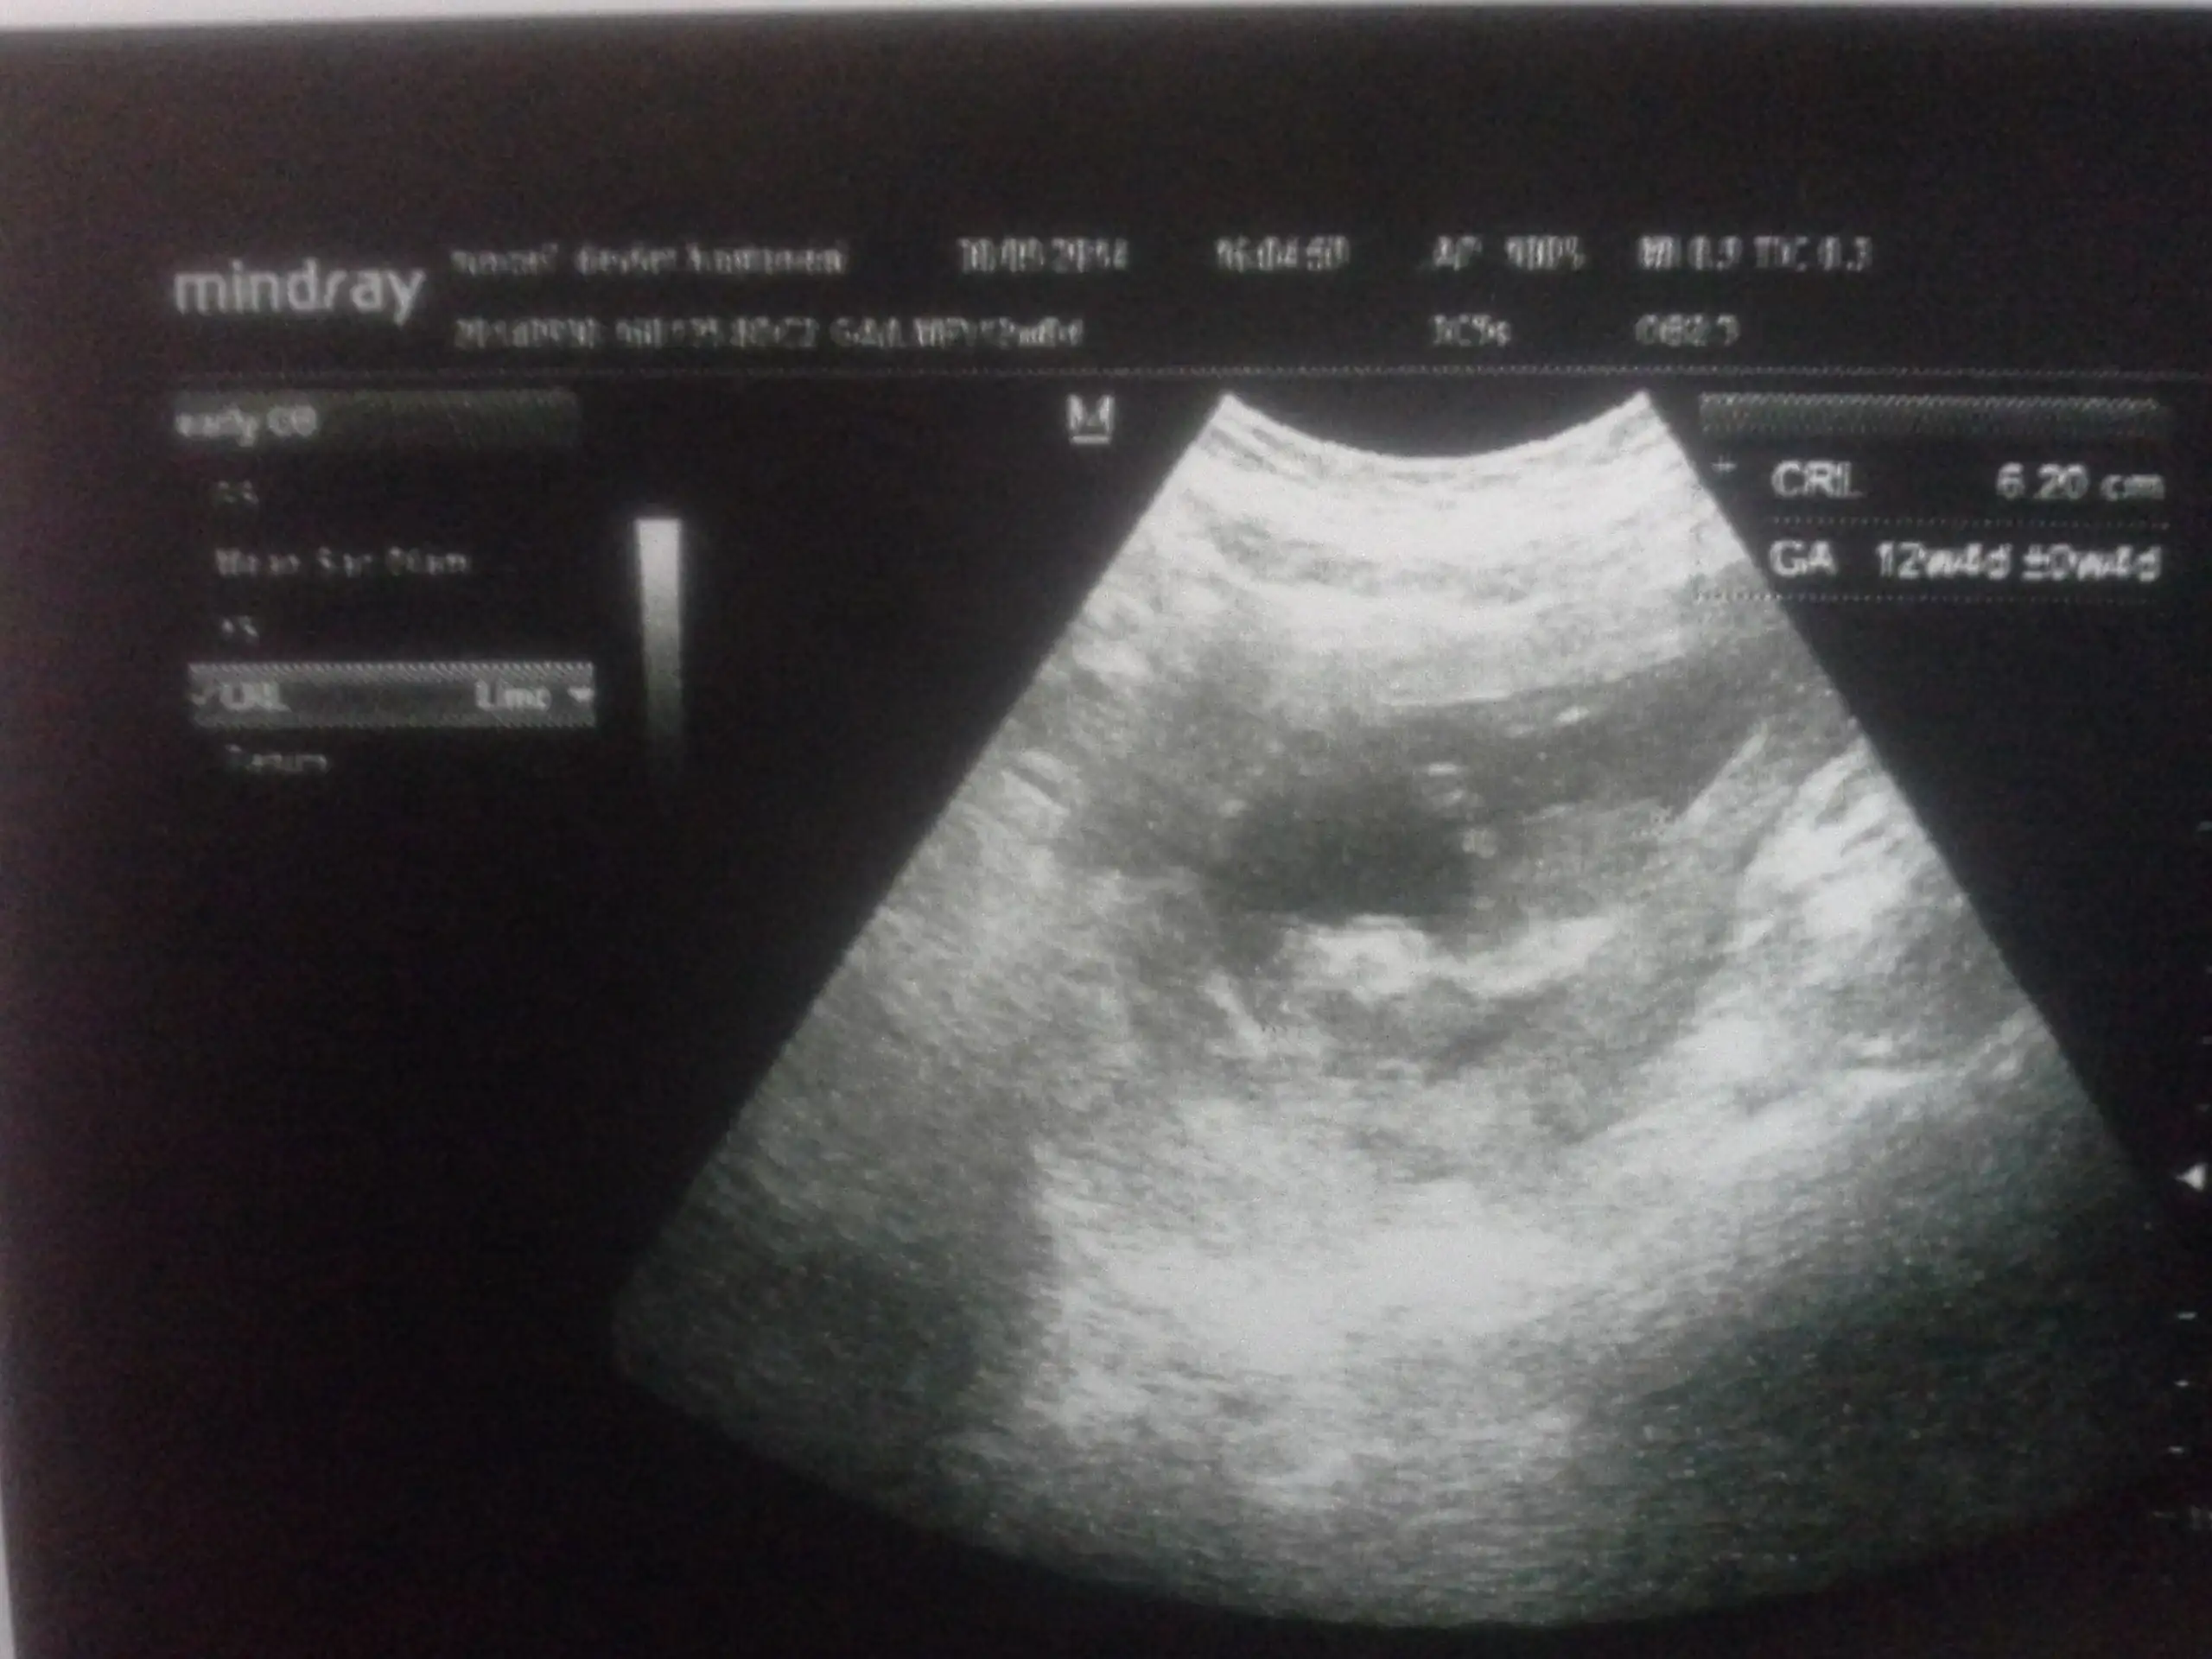

% 90 erkekArkadaşlar cinsiyet yorumu yapabilecek var mı? Lütfen yardım !!

Canim daha senin minnosun bacaklari bile tam cikmamis en iyi 12 ve 13 .haftalarda anlasilabiliyor:)Cevap verecek kimse yok mu![]()

Tesekkur ederim :))Canim daha senin minnosun bacaklari bile tam cikmamis en iyi 12 ve 13 .haftalarda anlasilabiliyor:)